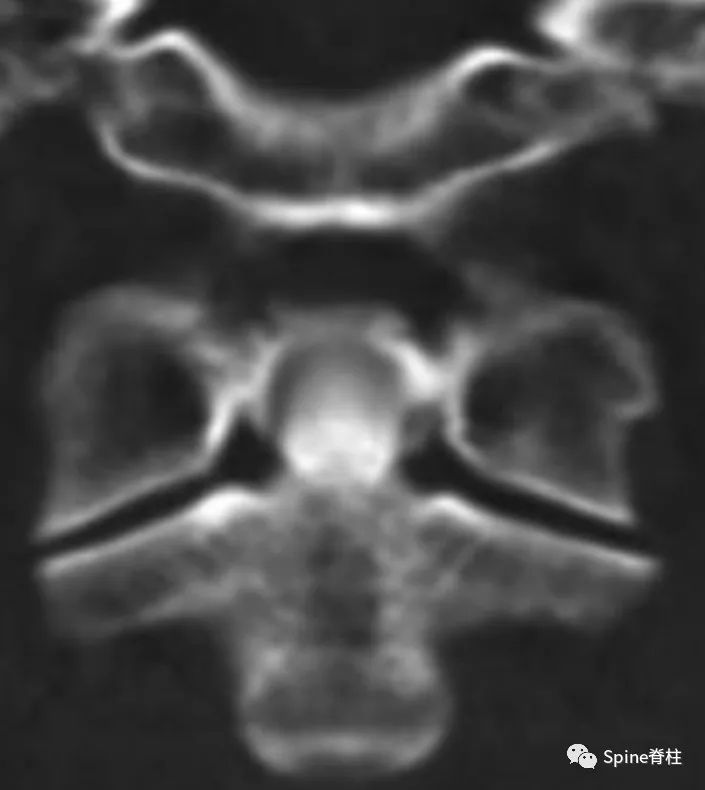

齿状突加冠综合征是指患者以急性颈痛伴随颈椎活动受限就诊,常伴发热,且影像学上表现为齿状突上方或周围出现大小不一、高密度、不规则的钙沉积影,但主要发生在齿状突后侧。因影像学征象犹如齿突戴上了一顶皇冠(如下图),因而得名齿状突加冠综合征,是因钙盐晶体在枢椎齿突周围软组织中沉积形成的。早在1985年,Bouvet等 (Arthritis Rheum, 1985) 首先报道此病。

颈椎CT冠状位重建显示犹如齿突戴上了一顶皇冠。故得名齿状突加冠综合征